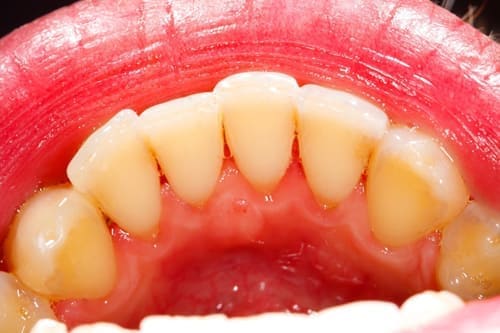

スケーリング前

-

スケーリング後